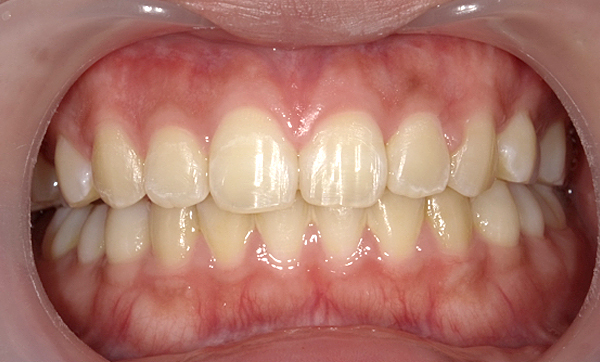

| 治療前 | 治療後 |

|---|---|

|